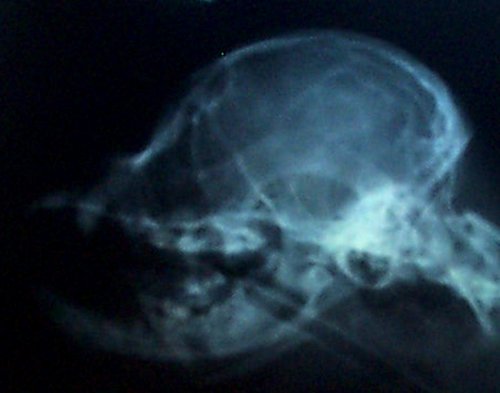

Based on my findings, a study was eventually done to determine

if a skull x-ray could be used to determine amount of CM. The

more CM, the more likely there is to be SM--in most cases. This

study did show there was one skull measurement that did indicate

amount of CM. Here is a comparison of two skull x-rays which

show why this particular measurement indicates amount of CM. The

top one is a skull x-ray of a Cavalier with severe CM (and has

SM as well) and the bottom one is a skull x-ray of a Cavalier

with very little to no CM (and no SM).

The line was drawn from right in front of the 'hole'

(black spot), center of that curved bone (the 'jaw hinge' area)

to where the most thickened area of the skull ends (and the

occipital area begins). In the dog with almost no CM and no SM

you can CLEARLY see there is a lot more lower backskull left

behind/below that line as compared to the dog above--which

literally has almost none! This also happens to be the area

where the cerebellum sits so it would be common sense that the

dog in the top x-ray would have much less room for the

cerebellum than the dog on the bottom--and therefore more CM (chiari

malformation). There just isn't any skull left for there to be

enough room for the cerebellum. It appears here that a good

skull x-ray may be very useful in determining amount of CM and

therefore breeding towards a goal of less and less CM in future

offspring and thereby lessening the prevalence of SM. A skull

x-ray is much cheaper than an MRI which will enable many more

breeders to x-ray for amount of CM in the future as more

information becomes available.